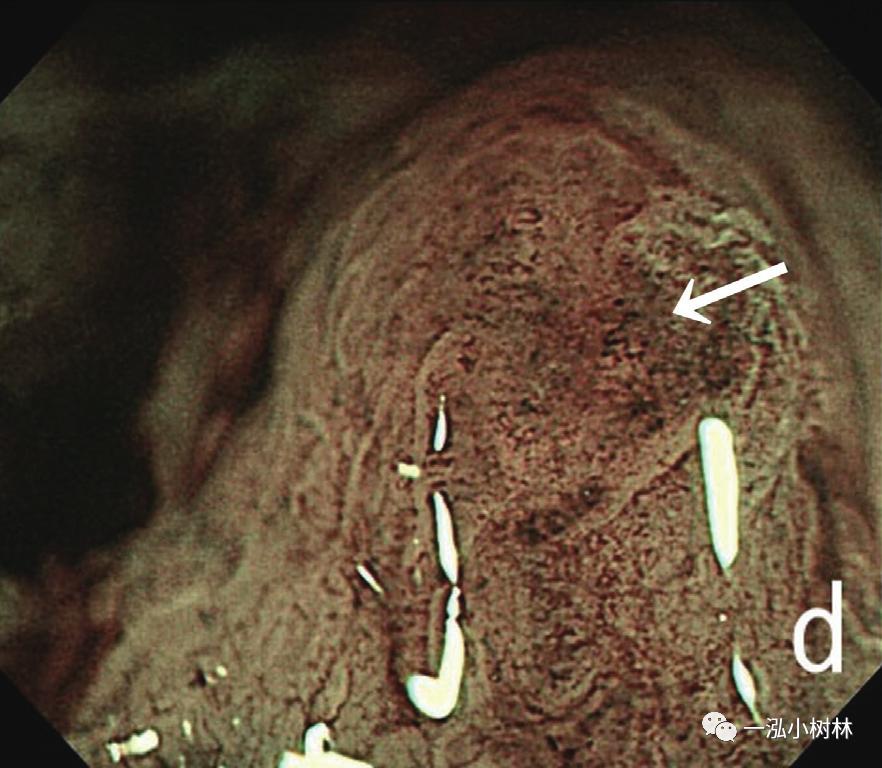

内镜检查(图1):胃黏膜整体粗糙、弥漫性隆起,易出血。在胃体下部、胃窦部黏膜的粗糙明显,散在小隆起,一部分也发现了较大的隆起性变化。ME-NBI视察即使残留着接近正常的腺管,表面微细结构的消失也很明显,在褪色区域也发现了血管的扩张和蛇行、腺管结构的紊乱。

图1d ME-NBI 贲门部 白区不清晰,微血管扩张、蛇形,分布不规则(箭头)。